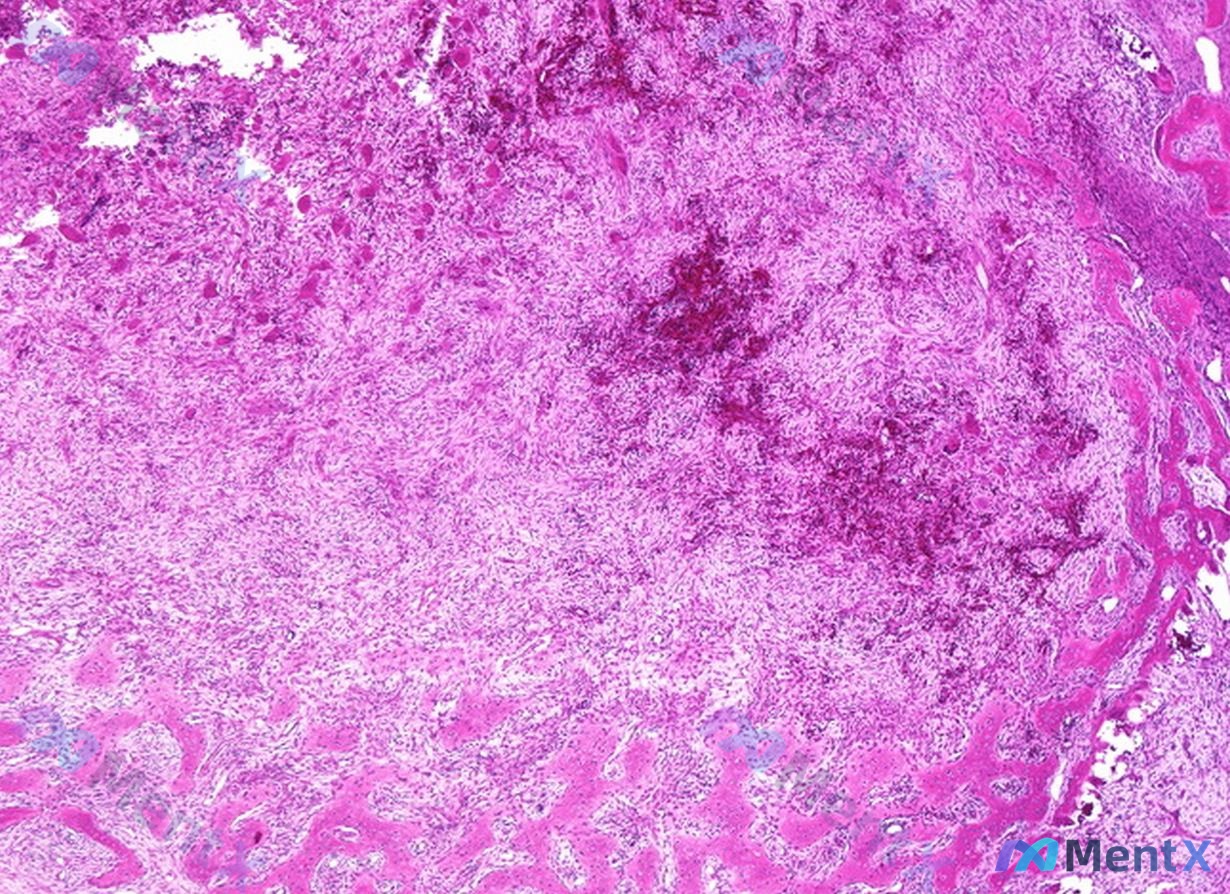

病例资料整理 患者信息:25 岁,女性。 主诉:5 个月前进门后左肩疼痛加剧。 既往史:2 年前曾因被地毯绊倒导致股骨骨折。 影像学检查: - 左肩 X 光:肱骨近端可见明显的溶骨性骨质破坏,病变区呈膨胀性生长,皮质变薄,骨小梁结构紊乱。 - 手腕 X 光:双侧手部及腕部骨密度普遍减低,多个掌骨及指...